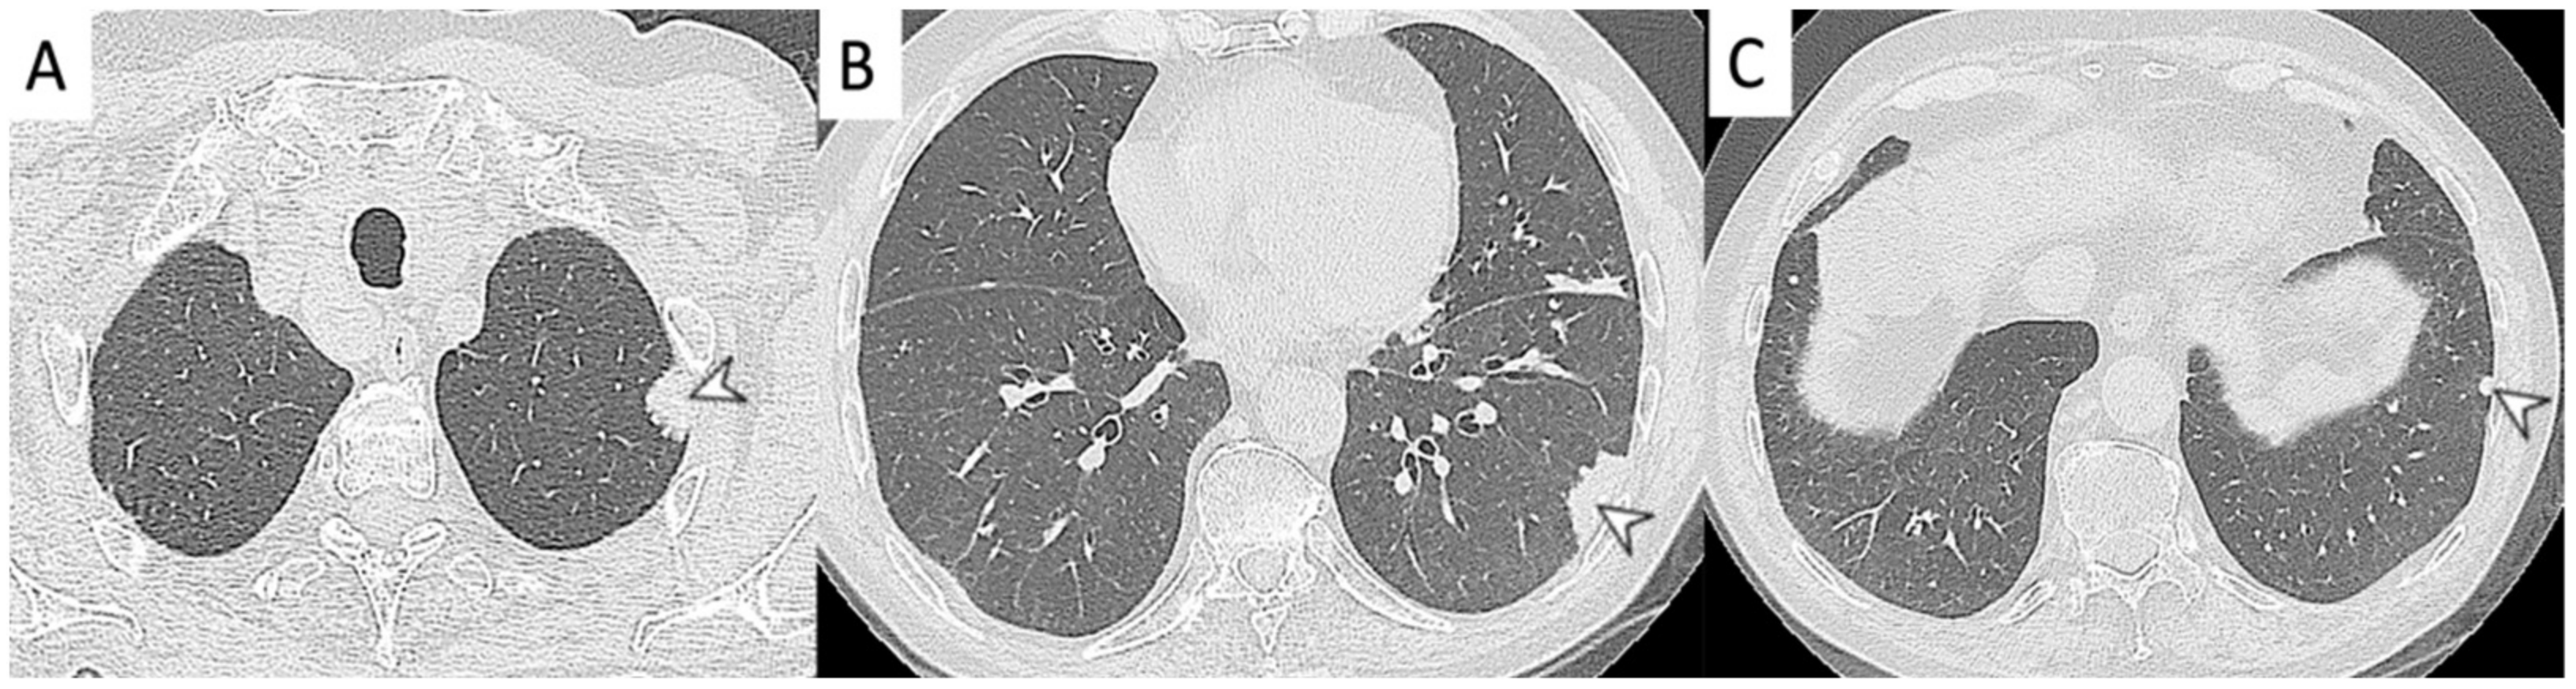

2.4. Granulomatosis with Polyangiitis (GPA-Wegener’s Disease)

| GPA | Solid nodules, GGOs due to hemorrhagic alveolitis (common); halo sign, crazy paving (less common) |